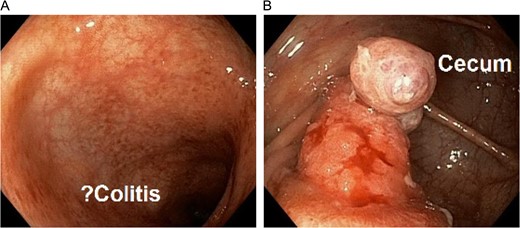

CT with oral and IV contrast demonstrated cecal thickening without visualization of the appendix (Fig. 1). A colonoscopy was performed, which showed mild diffuse erythema and edema in the last 40 cm of the ascending colon as well as a mass within the lumen of the cecum (Fig. 2). Biopsies of the colon demonstrated chronic active colitis and ulceration of the cecal mass, suggestive of mild UC (Fig. 3, bottom right and left). No granulomata were present, and there was no evidence of dysplasia. The decision was made for operative management due to continuation of her symptoms and need for definitive diagnosis.

(Top left) Laparoscopic identification of the cecum with invagination of the appendix. (Top right) Ileocecectomy gross specimen with intussuscepted appendix within the cecum. (Bottom left) Microscopic section of the appendix with ulceration of the mucosa. (Bottom right) Biopsy of left colon demonstrating cryptitis and crypt abscesses.

Laparoscopic assisted ileocecectomy was performed revealing an inverted appendix protruding into the cecal lumen (Fig. 3, top Left and right). The patient recovered quickly and without complications and is currently taking mesalamine for her UC.